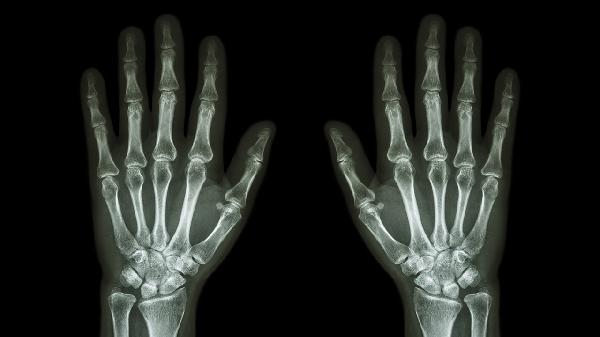

手指关节外伤后可能出现骨折、韧带损伤等情况,需通过X线或MRI明确损伤程度。急性期可进行冰敷制动,骨折需手法复位或内固定手术,韧带损伤可能需关节镜修复。